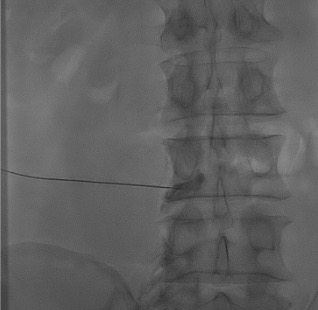

AP + lateral confirmation

Contrast injection — "Christmas tree"